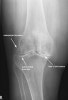

선 자세에서 무릎을 쭉 펴고 AP view를 찍으면 관절관격이 좁아진 것이 보입니다.

퇴행성 관절염의 이상 소견은 비대칭적 관절간격 좁아짐(joint space narrowing), 골경화(subchondral bone sclerosis), 관절주위낭종(subchondral cyst), 골극(osteophyte, spur)입니다.

대퇴슬개관절과 대퇴경골관절의 전반적인 상태는 lateral view와 axial patellofemoral view로 확인합니다.

추가로 무릎을 40도 정도 구부리고 선 자세에서 AP view를 찍으면 경골과 대퇴골의 서로 다른 체중 부하부위가 보이므로 관절면의 좁아짐을 관찰할 수 있어서, 관절염에서 가장 감수도가 높은 검사법입니다.

Tunnel view(다른 말로 intercondylar notch view)에서는 종종 골극, 골연골 유리체가 보입니다.

X-ray : 무릎 관절염(Knee Osteoarthritis)